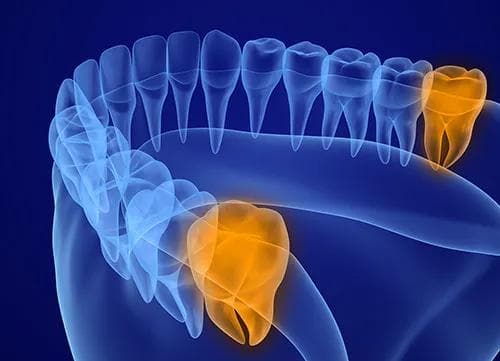

Visdomstenner

Visdomstenner som ikke har nok plass, er en kjent årsak til smertefull betennelse. Dette kan også føre til tannbyll og bakterievekst som er vanskelig å vedlikeholde selv. Hvis smertene er sterke bør du oppsøke akutt tannlege.